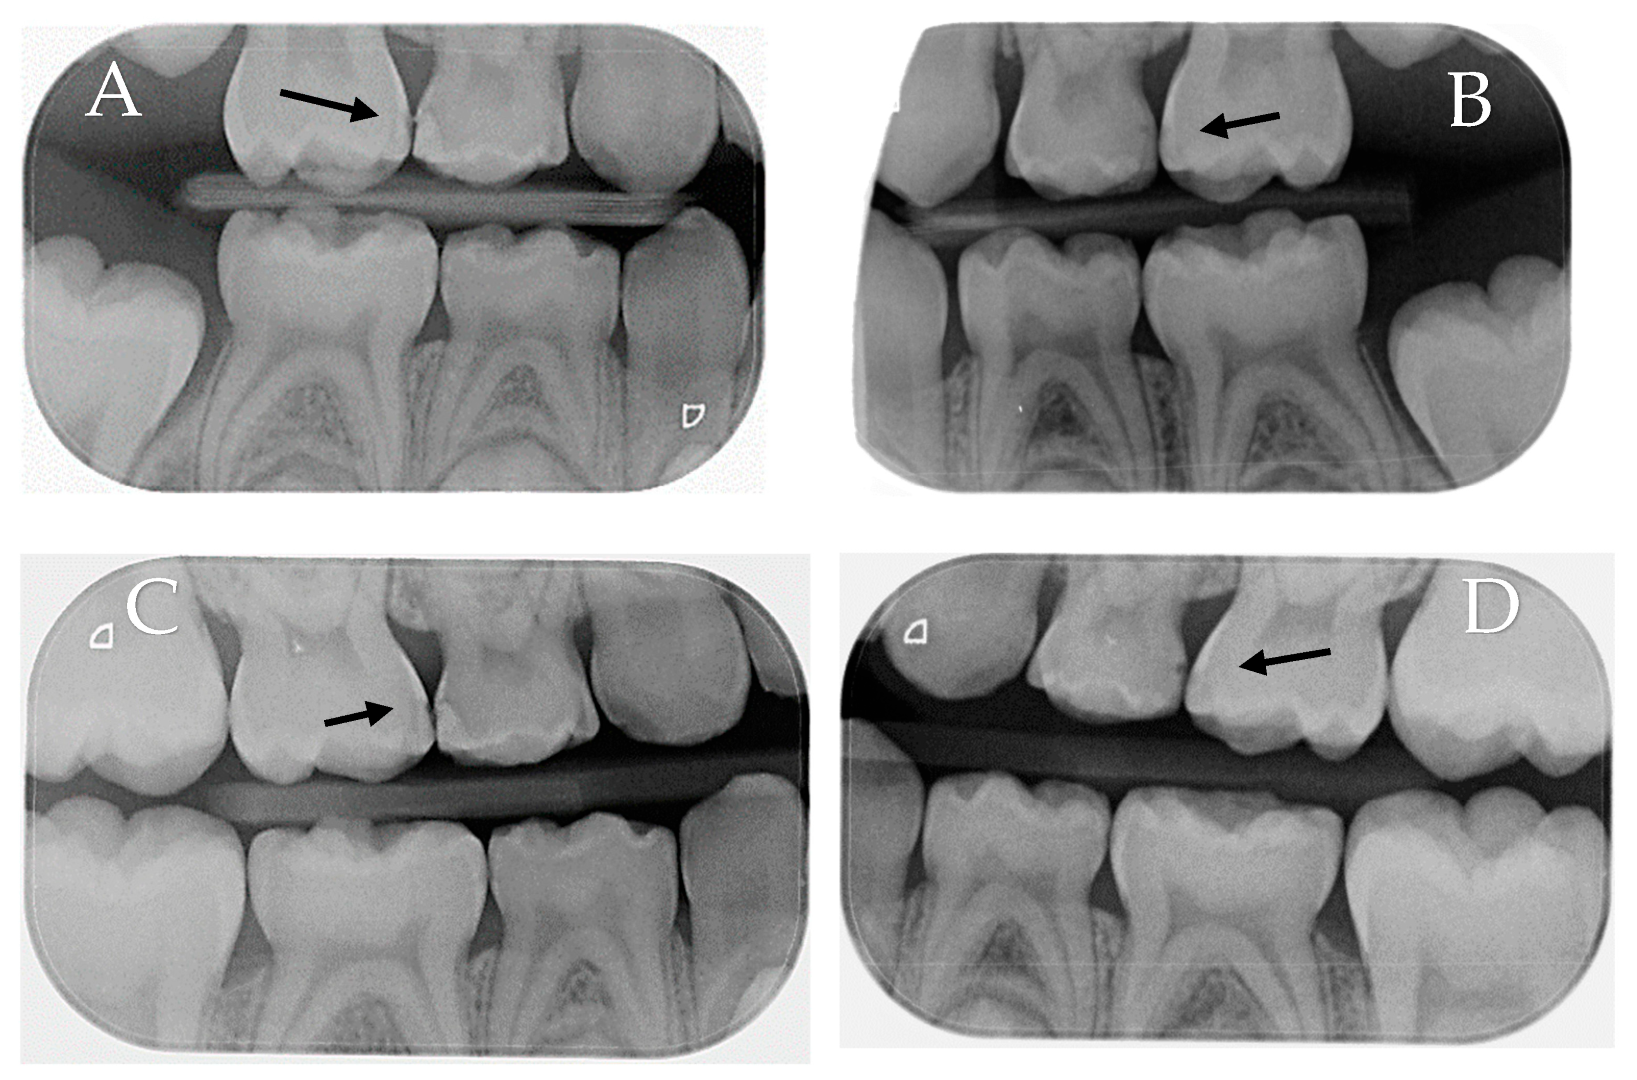

The findings of the radiographic scores obtained by both the experimental and control groups at the baseline and the 6- and 12-month follow-up visits exhibited a tendency that was comparable to that observed in the ICDAS II; nevertheless, there was no statistically significant difference between the two groups in the radiographic scores at the baseline and follow-up visits. Figure 4 is an illustration of the lesion evaluation using radiographs.

Figure 4. Bitewing radiographs of the same patient at the baseline and after 12 months. (A): #55 (control) at the baseline mesial carious lesion (E1). (B): #65 (experimental) at the baseline mesial carious lesion (E2). (C): #55 (control) after 12 months mesial carious lesion showing slight progression (D1). (D): #65 (experimental) after 12 months mesial carious lesion without progression (E2).